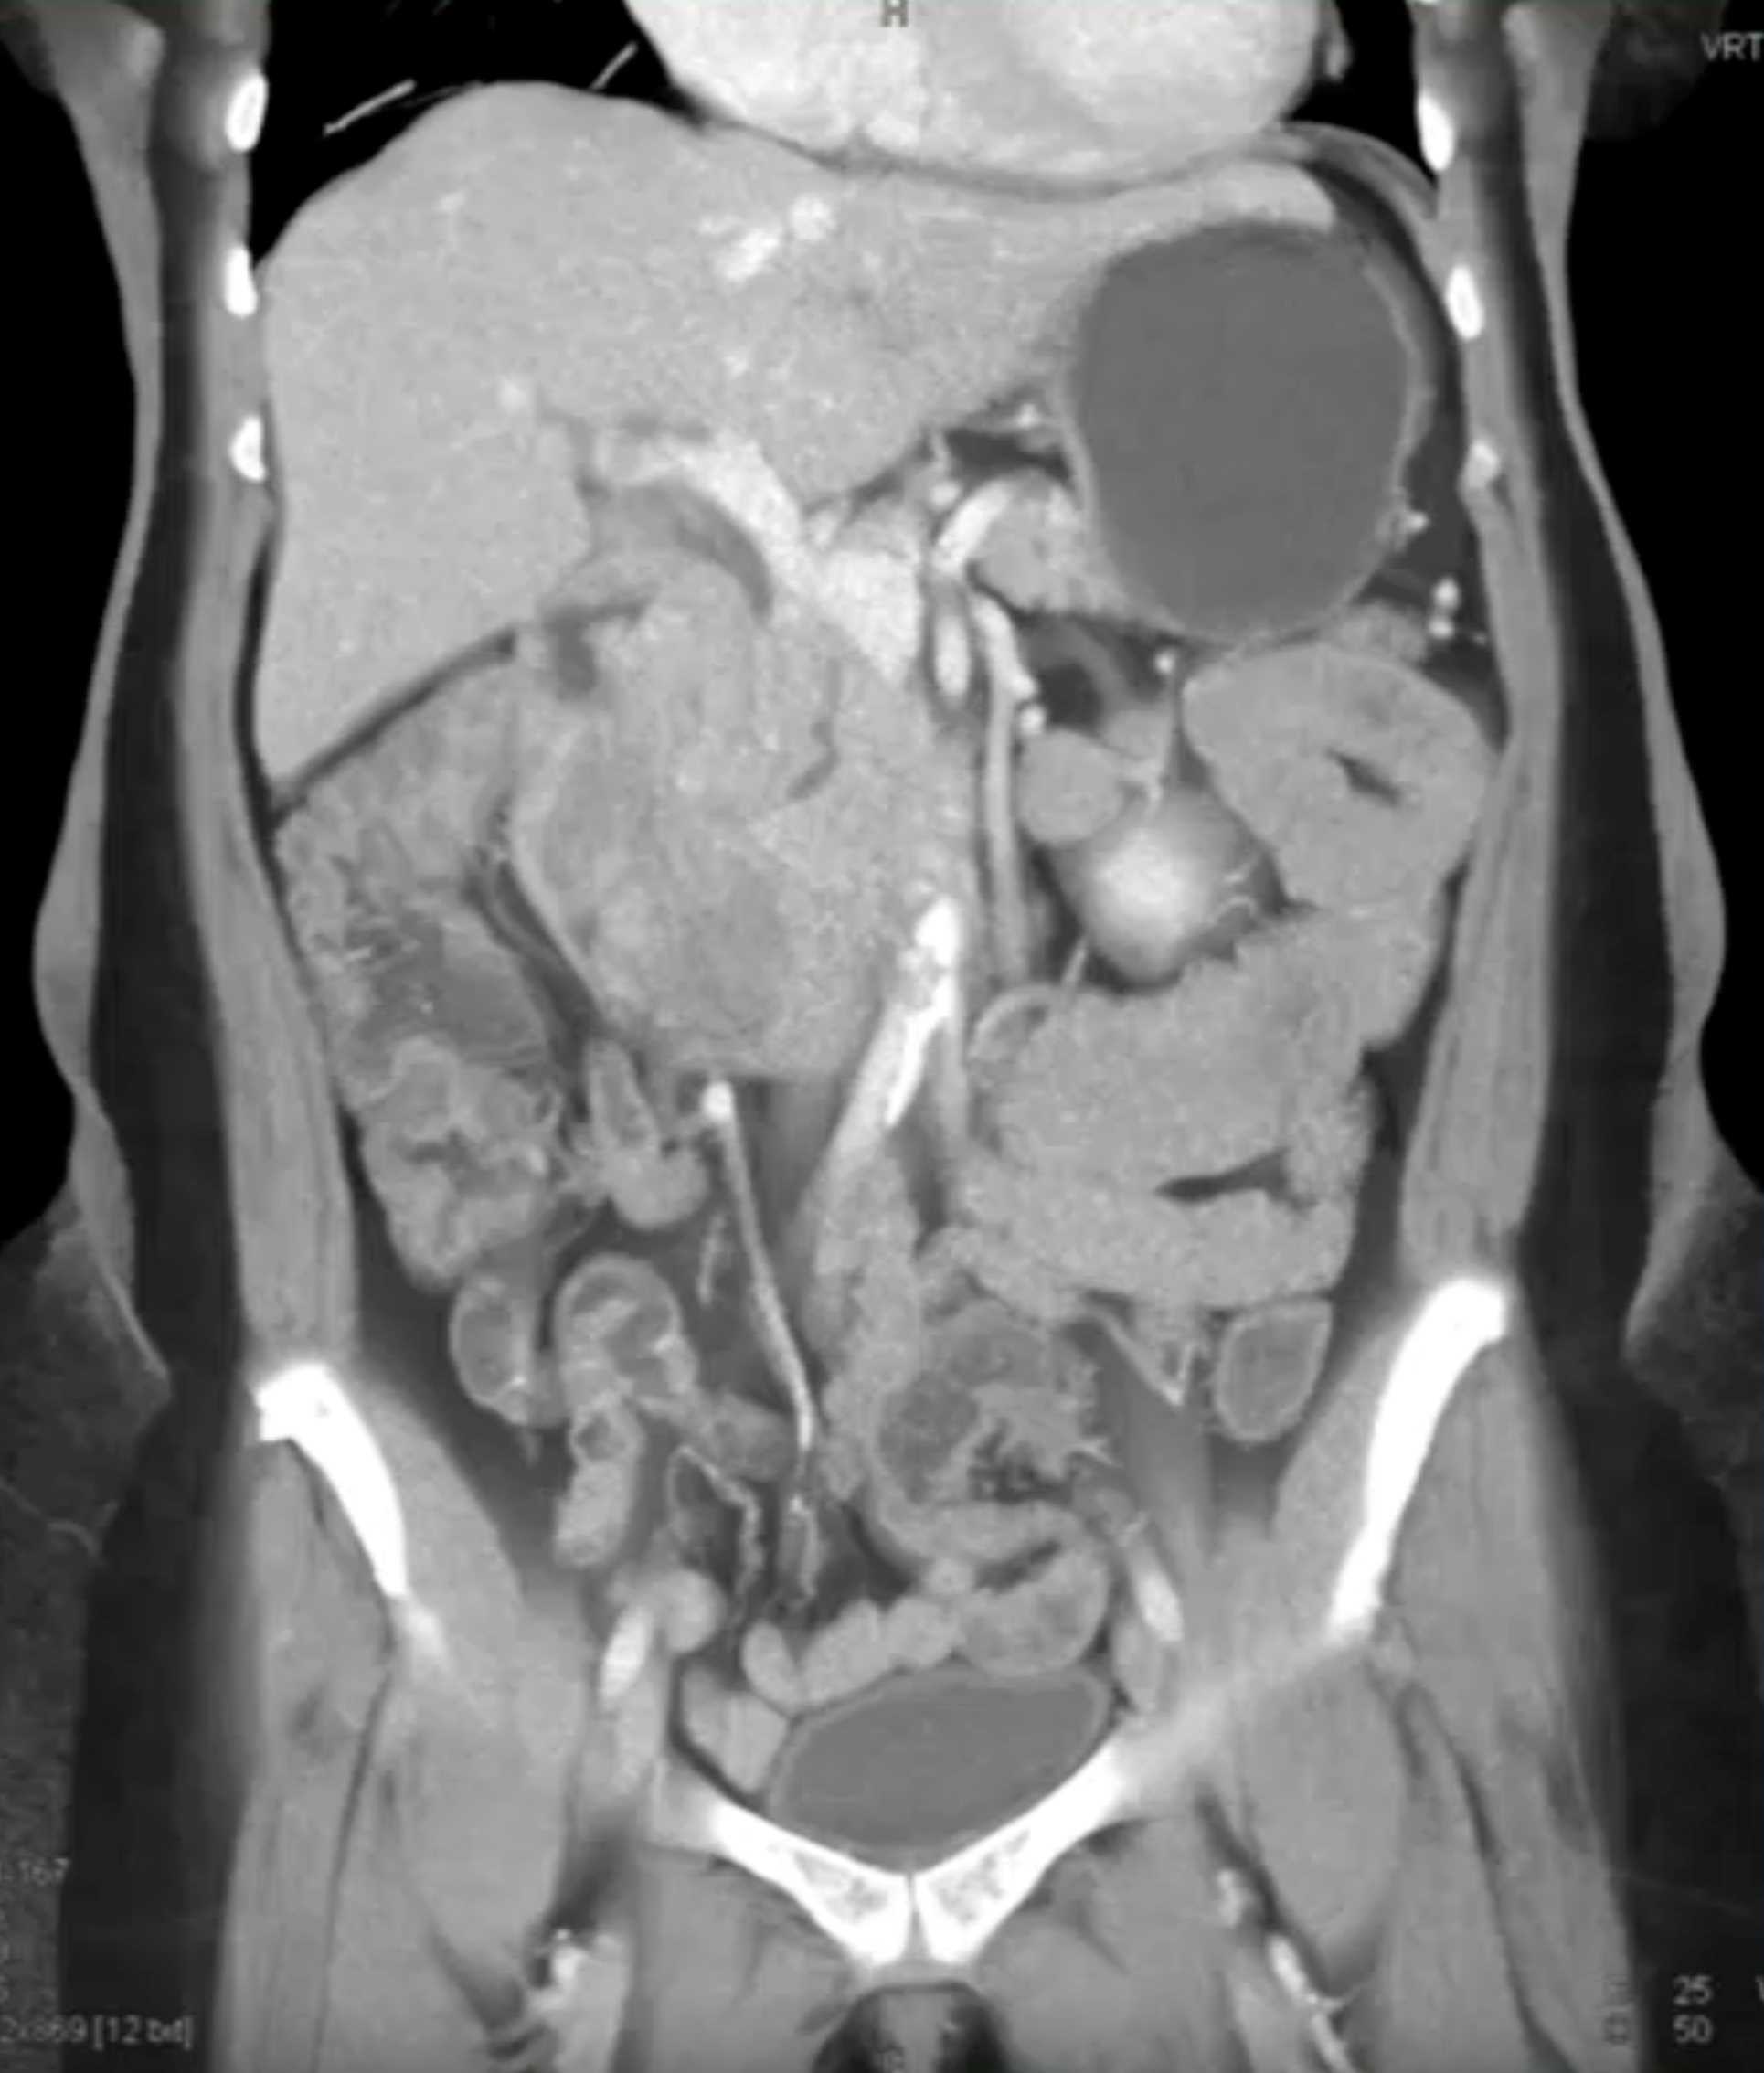

Lagre Gastric GIST Tumor